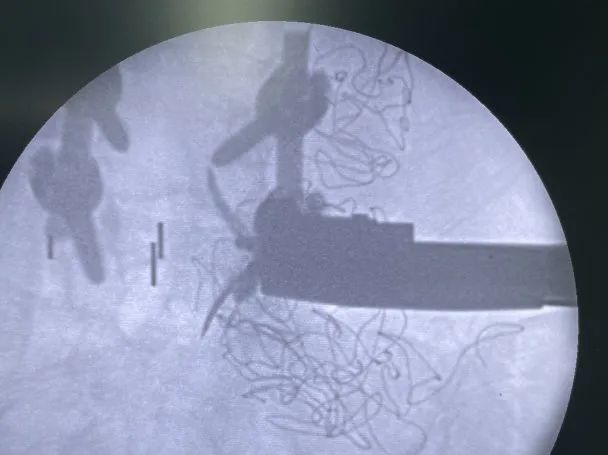

術中影像

- L3/L4常規OLIF融(rong)合器植入

- L3/L4 、L4/L5椎間植骨

- 最終透視

- 術后一周左右,將根(gen)據(ju)情況,擇期為患(huan)者拆除、更換后路(lu)釘棒系統